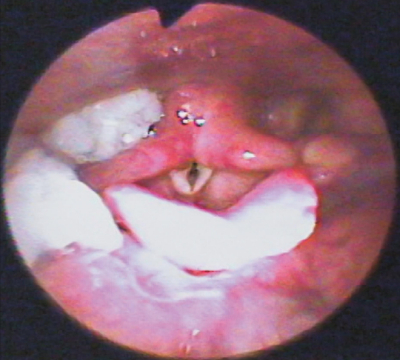

79 歳の男性。食事摂取の困難を主訴として来院した。水でむせやすくなり、食事時間が長くなってきたという。嚥下反射の惹起は良好である。米飯摂取後の嚥下内視鏡検査の画像を別に示す。

この状態を改善させるのはどれか。1つ選べ。